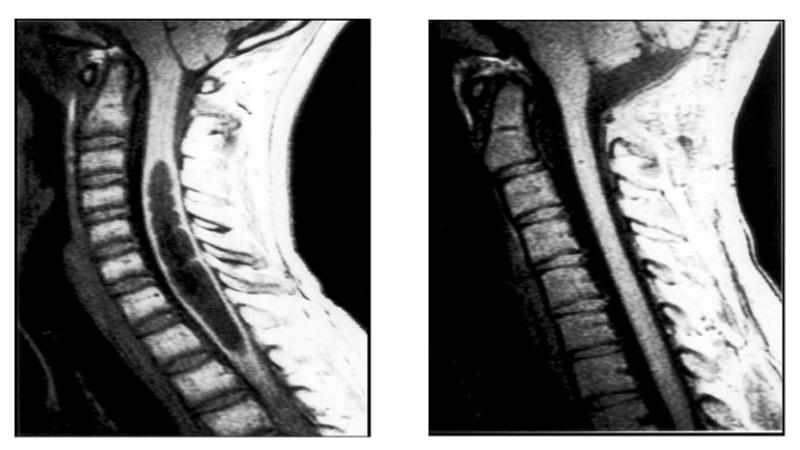

Для установления точного диагноза необходимо обратиться к врачу-неврологу. Этот специалист основывает свои выводы на данных, полученных с помощью компьютерной и магнитно-резонансной томографии. Исследованию могут подвергаться различные отделы позвоночника: грудной, шейный, а в редких случаях и поясничный.

Диагностика сирингомиелии обычно включает в себя магнитно-резонансную томографию (МРТ), которая позволяет визуализировать наличие кист в спинном мозге. Также могут быть проведены неврологические тесты для оценки функции нервной системы.